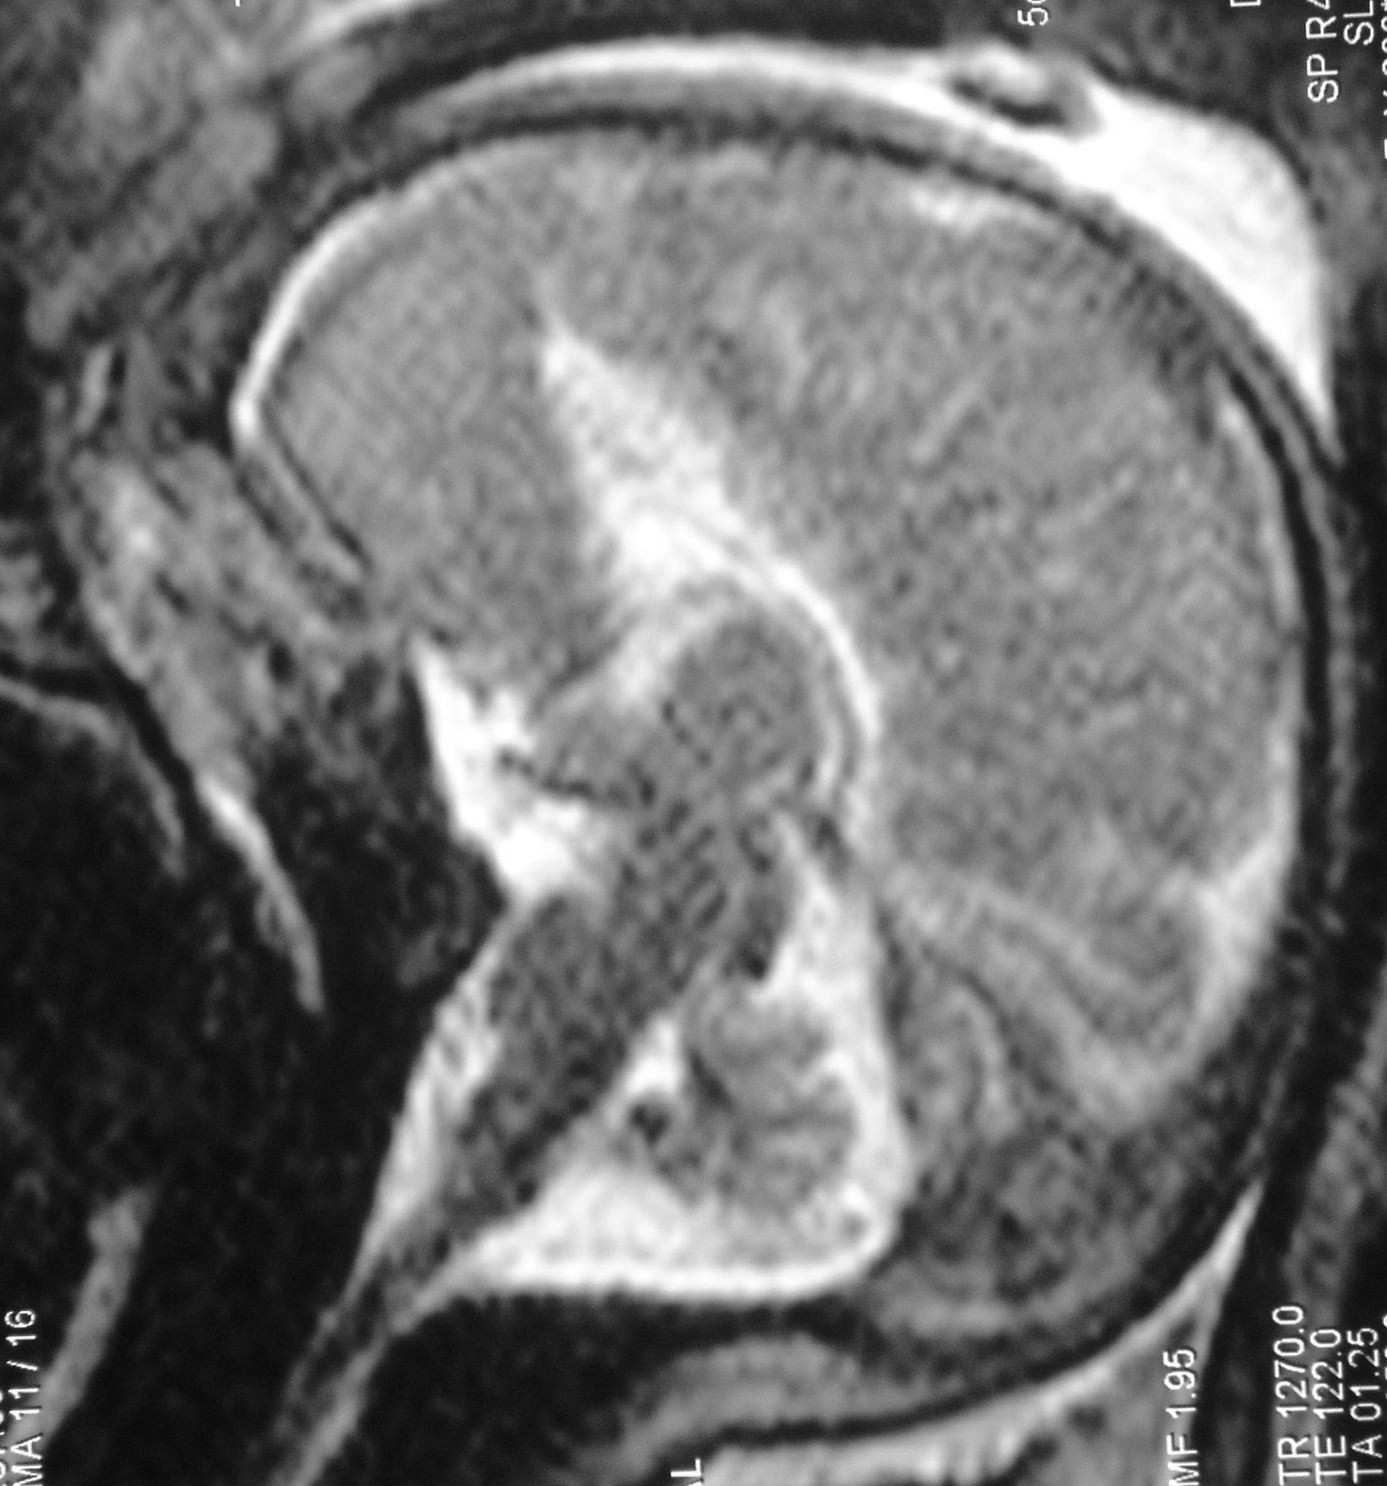

l’IRM

elle permet d’étudier le cerveau, mal vu en échographie

elle est surtout utile dans les brachycéphalies, pour rechercher un retentissement cérébral (engagement tonsillaire, hydrocéphalie) ou d’autres anomalies cérébrales associées (cf. ci-contre : dysplasie orbito-fronto-nasale avec agénésie du corps calleux).